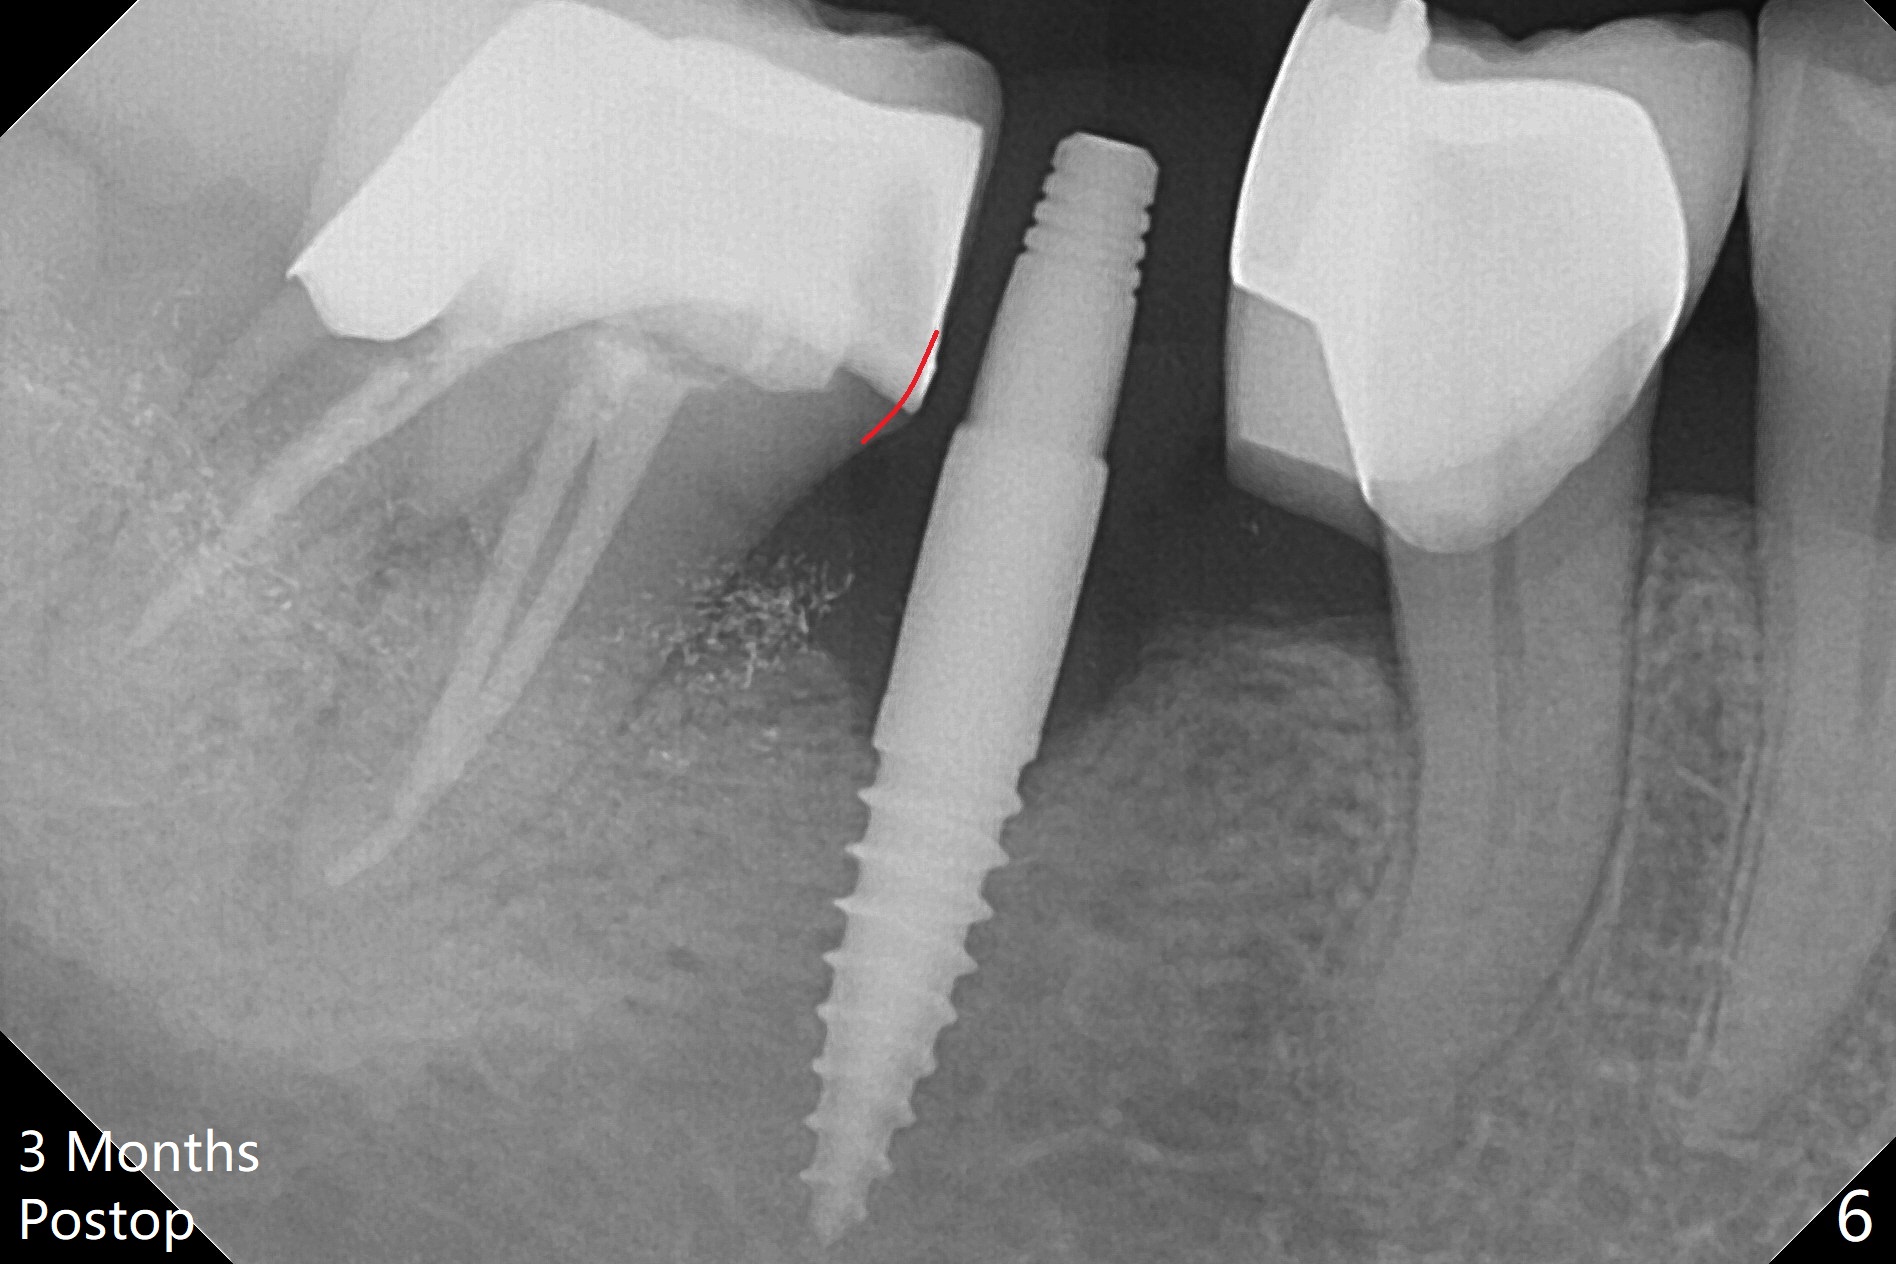

There is a space underneath the pontic at #30 (Fig.1 *), the basis for food impaction. After sectioning between the pontic and the posterior retainer, the pontic is removed from the anterior retainer with an attachment (Fig.2 *). The initial depth of osteotomy is 10 mm following ridge top reduction (Fig.3). A 3x10(4) mm 1-piece implant is placed with >50 Ncm; to reduce possibility of crown dislodgement from the implant, the retainers will be kept with modification of the proximal surfaces as shown by curved lines in Fig.4. Periodontal dressing is applied after suturing. There is no postop paresthesia. The periodontal dressing remains in place 2 weeks postop because of engagement into the attachment slot and undercuts (Fig.5). The patient returns 3 months postop; after minor contour adjustment (Fig.6 red curved line), impression is taken. The permanent crown is temporarily cemented (3.5 months postop) in case of food impaction due to the distal overhang of the tooth #29 (Fig.7). In fact the patient returns 4.5 months post cementation with right TMD (muscle relaxant prescribed) and food impaction, although there is no bone resorption (Fig.8,9). It appears that the crown at #29 needs to be redone, while porcelain will be added to the mesial surface of the one at #30 (Fig.10 red lines). In fact the crown at #30 is redone because of loose proximal contact with #31; there is no bone resorption 13 months post cementation (Fig.11). Bone resorption remains unnoticeable 28 months post cementation (Fig.12,13).